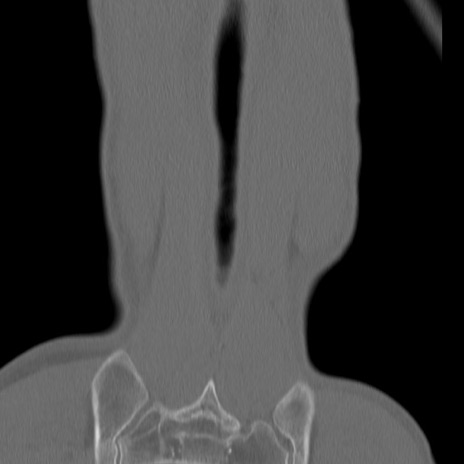

症例3 腰椎CT(冠状断像)

腰椎CT

矢状断像